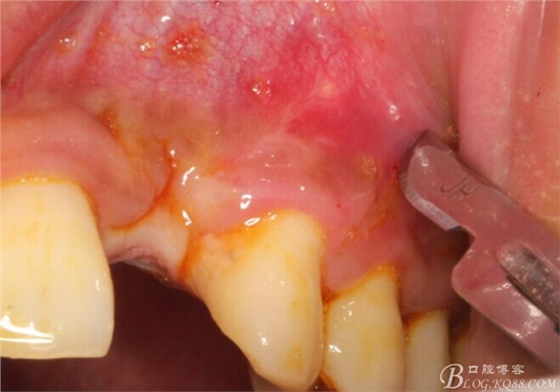

于是我果斷告知患者,手術(shù)失敗了,不能拖延,如不及時(shí)處理,炎癥繼續(xù)發(fā)展會(huì)很快波及鄰牙牙槽骨。患者接受我的建議。切開翻瓣,骨粉及生物膜消失了,骨吸收嚴(yán)重,幸運(yùn)的是,因?yàn)樘幚砑皶r(shí),鄰牙骨支持依然存在。